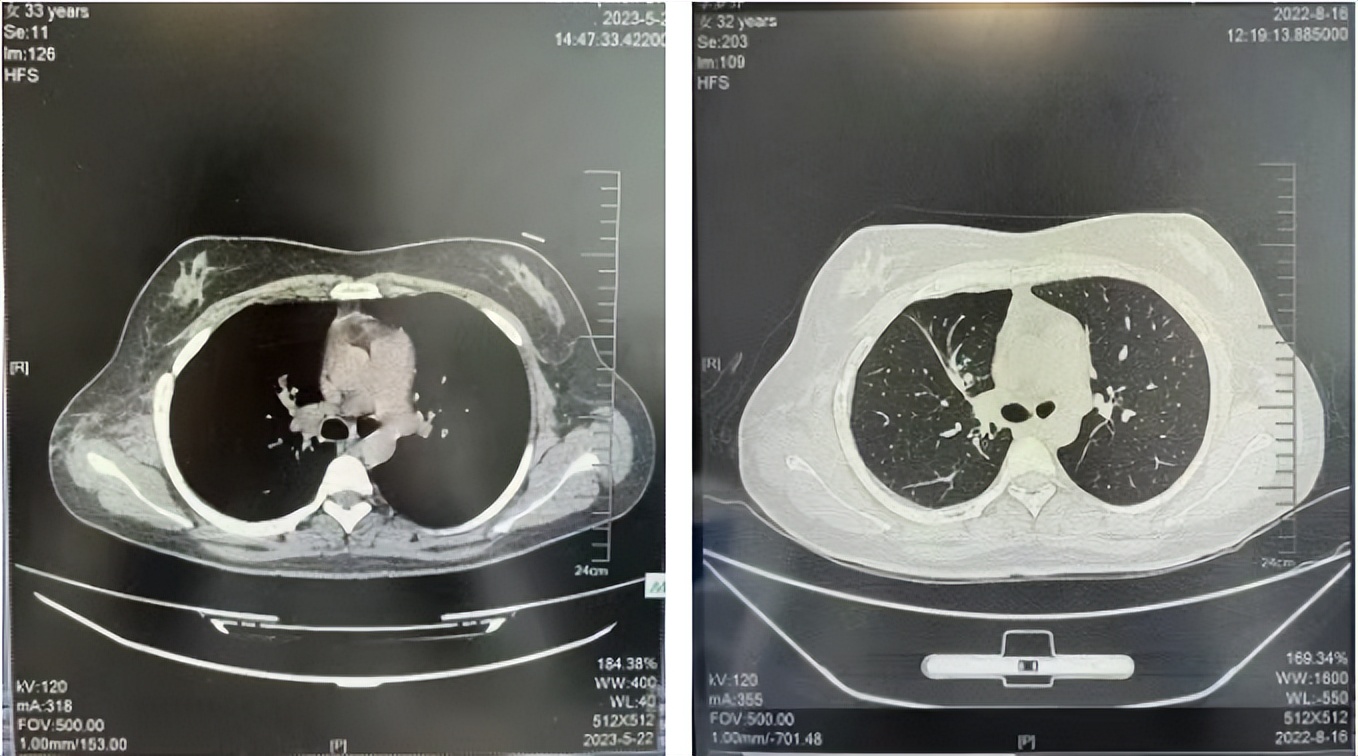

2016年1月复查CT提示支气管截断可见新发小结节,一线治疗采用培美曲塞+DDP方案化疗4周期(培美曲塞3.36,DDP 480mg)。化疗后复查胸部CT:右肺见不规则结节样影,最大层面大小约19mm*8mm,较前比较明显增大,疗效评估PD。2017.3-2017.4予单药多西他赛化疗3周期,疗效评估SD。2018年5月末复查CT提示结节较前增大,评效为PD,2018年6-10月予多西他赛+CBP化疗4周期,疗效评估SD。2022年5月患者出现活动后气短,复查胸部CT示右肺膨胀不良;右侧胸腔积液增多。胸腔积液包埋病理示符合肺腺癌细胞。行NGS基因检测:EML4:exon13-ALK:exon20融合。PD-L1(克隆号22C3)TPS<1%。

2018.07

2022.05

2022.08

2023.05